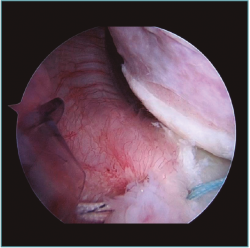

A excepción de los pacientes con significativos déficit óseos o recidivas con una mala calidad de tejido capsular, realizamos una técnica de reparación artroscópica. Operamos siempre con el paciente en decúbito lateral, con anestesia regional y general. Utilizamos siempre 4 portales instrumentales y un portal superior visual de exploración. Comenzamos nuestras cirugías con un portal de visión posterosuperior y un portal anterior de trabajo. Dependiendo de los hallazgos, realizamos las plicaturas capsulares que sean necesarias. En repetidas oportunidades encontramos hiatos intracapsulares, como por ejemplo entre el ligamento glenohumeral medio y superior, o laxitudes capsulares centrales, tratando los mismos con suturas de superior a inferior para generar una plicatura similar al capsular shift, incluso aumentando el espesor capsular (Figura 3). Luego de reparar estos defectos capsulares, seguimos nuestras plicaturas desde posterior, a través de un portal posteroinferior accesorio, colocando un anclaje con doble sutura, realizando la reparación y/o plicatura del haz posterior del ligamento glenohumeral inferior y achicando el receso inferior agresivamente siempre con anclajes de doble sutura (Figuras 4 y 5). Luego pasamos a un portal superior de visualización, dedicamos el tiempo necesario a liberar todo el labrum anteroinferior, despegando la cápsula anterior y el labrum del subescapular para movilizar e incluso acortar la cápsula, en ocasiones resecando parte de la misma para mejorar la plicatura; siempre utilizamos una sutura de tracción anterosuperior por fuera de la cánula para traccionar el tejido. Para poder llegar lo más cercano a hora 6, el primer anclaje anterior lo colocamos por un nuevo portal percutáneo transubescapular, utilizando arpones doble sutura, usando el primer par de suturas para llevar la cápsula y el labrum hacia la glena realizando sobre esta una sutura doble de tipo colchonero para mejorar la aposición capsular (Figura 6). Luego colocamos en la mayoría de los casos 2 anclajes más para terminar la reparación, en general 4 arpones. De haber un intervalo de rotadores amplio, no vacilamos en cerrarlo con suturas (Vídeo anexo).

Figura 3. Visión desde portal posterior del hombro derecho. Paciente con inestabilidad glenohumeral y gran laxitud anterior. Se visualizan 3 plicaturas lado a lado generando un acortamiento y engrosamiento de la cápsula.